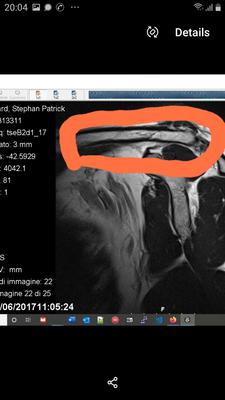

I have a dislocated sternoclavicluar joint, a dislocated first rib at the intercostal joint.